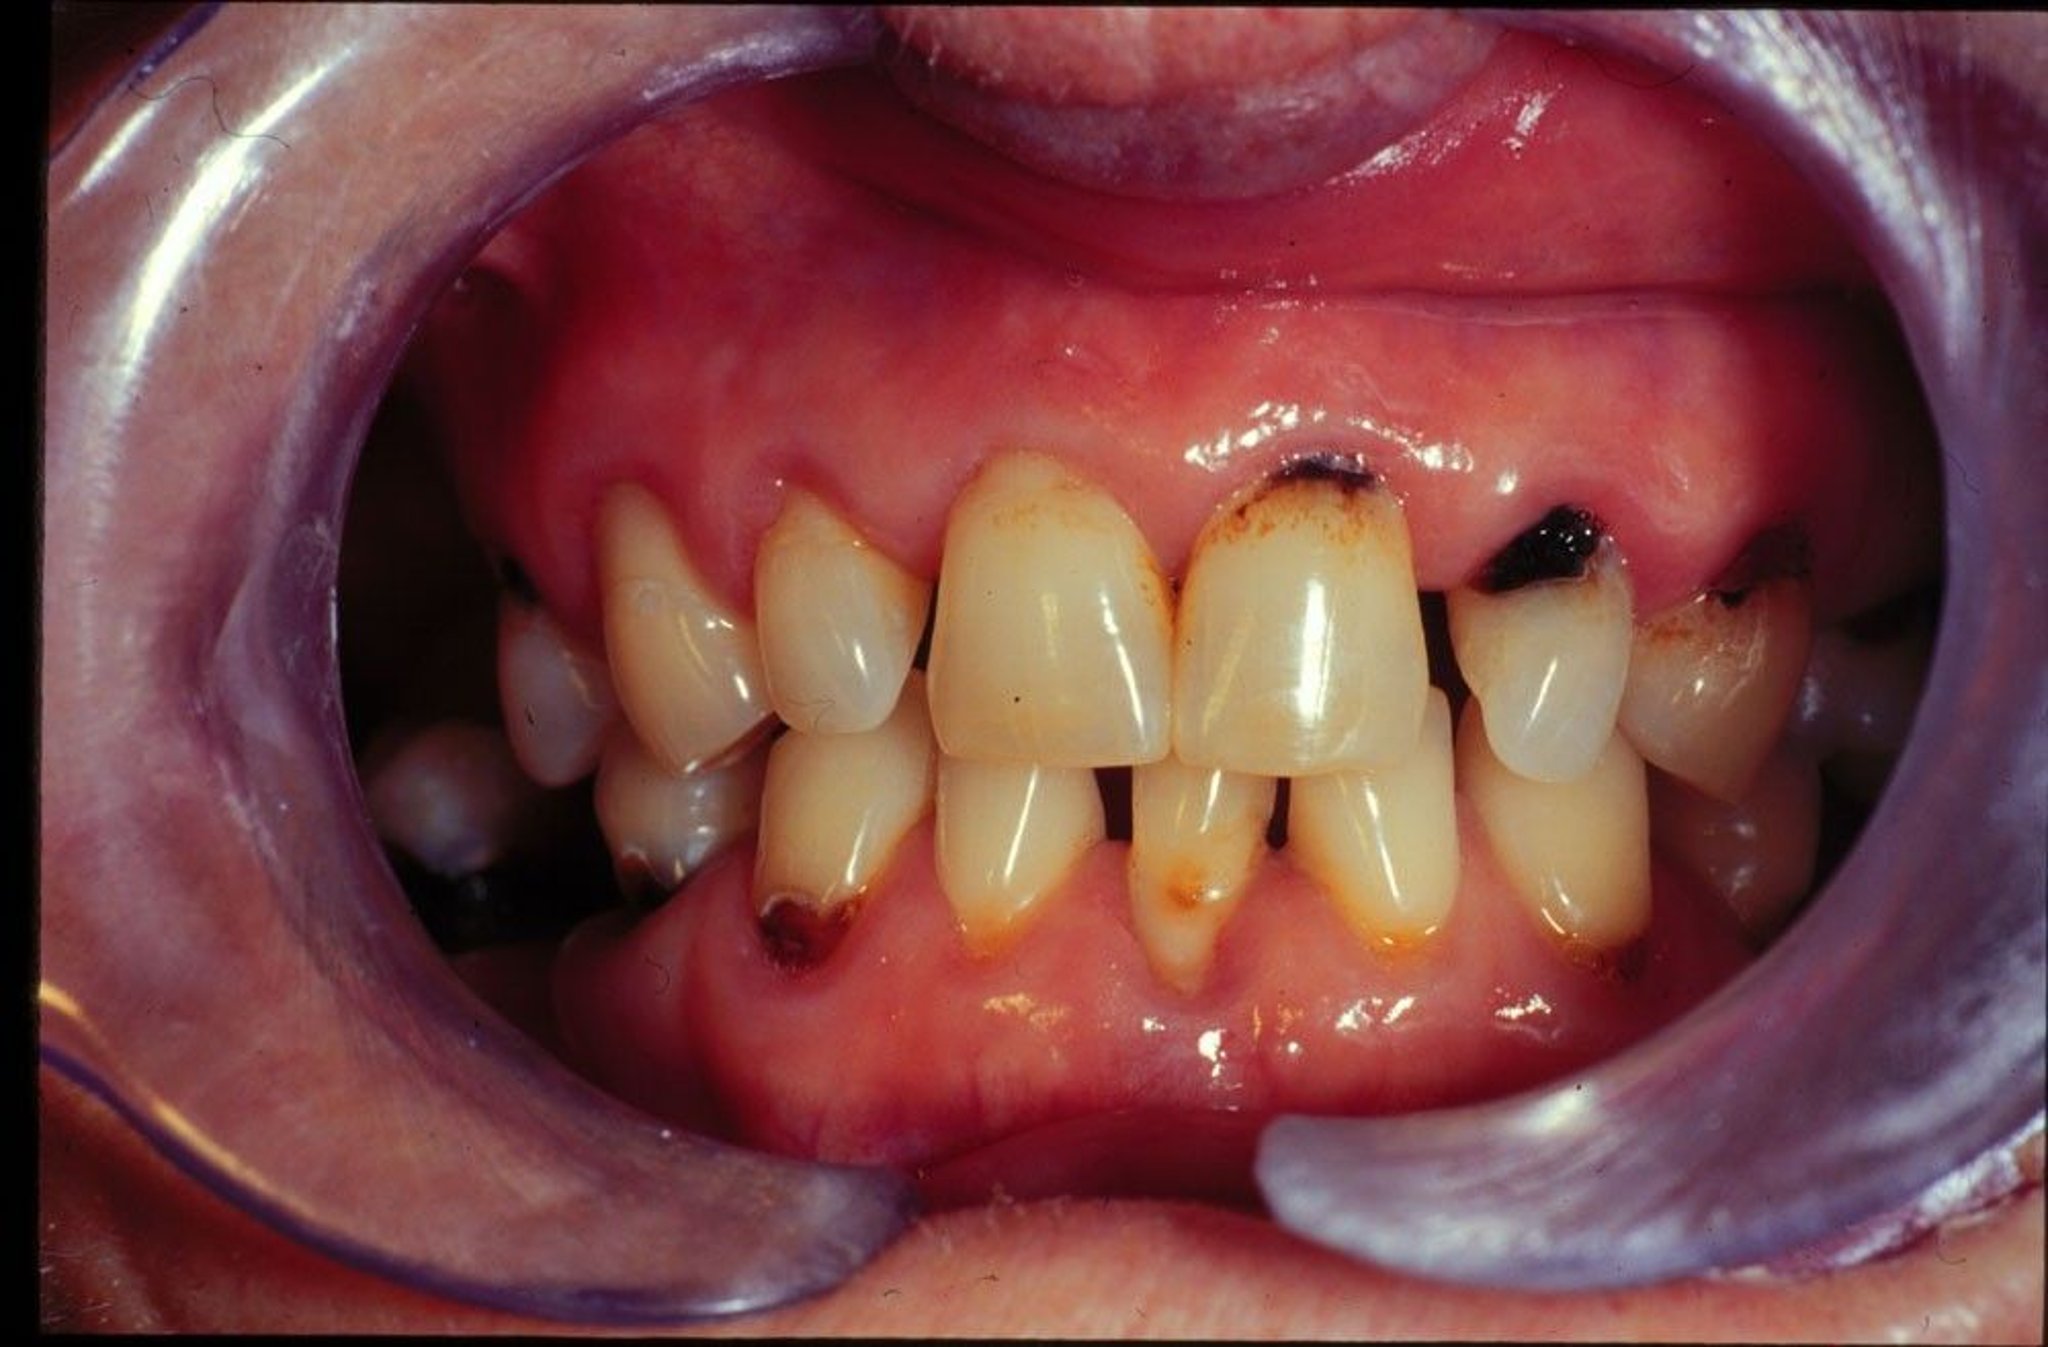

Bakteri, air liur (ludah), dan potongan makanan membentuk lapisan tipis yang disebut plak yang menempel pada gigi Anda. Plak mengeras seiring waktu dan berubah menjadi karang gigi. Karang gigi biasanya berwarna kuning. Anda terkadang melihatnya di dasar gigi. Bakteri yang hidup di plak dan karang gigi sulit dihilangkan.

• Memiliki banyak plak dan karang gigi di mulut Anda

• Memiliki gusi yang menyusut di bagian bawah gigi Anda (gusi yang menurun)

Lubang dangkal pada enamel Anda tidak sakit. Gigi berlubang yang sedikit lebih dalam bisa menyebabkan rasa sakit saat Anda mengonsumsi makanan atau minuman panas, dingin, atau manis.